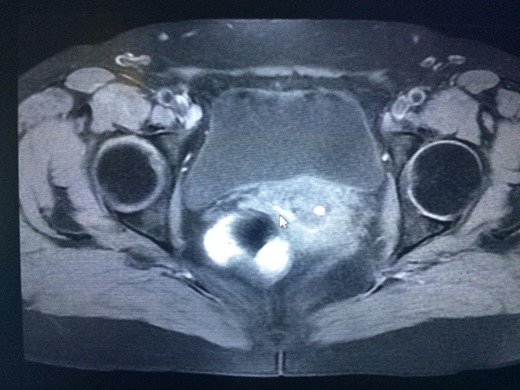

The colposcopy revealed a spot with inflammation at the left upper of the vagina, while the transvaginal ultrasound did not reveal any abnormalities. The colonoscopy did not reveal any tumor, but diverticulosis of the rectosigmoid colon with mild inflammation was found. The pelvic MRI showed multiple diverticula in the sigmoid colon, and one of them with a fistula tract of ~3 cm reaching the posterior wall of the vagina (Fig. 1).